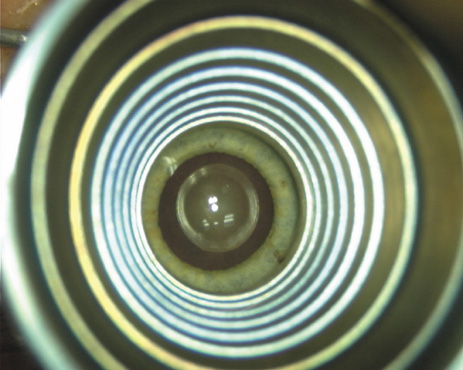

All incisions are paired, except in the case of very low ATR astigmatism

wherein a single 35-degree nasal LRI is placed opposite to the single-plane

temporal clear-corneal phaco incision. Paired incisions are preferred

to optimize symmetric corneal flattening and are expressed in

degrees of arc rather than chord length. This is done in order to diminish

over- and undercorrections for unusually small or large corneas, because

corneal diameter may significantly impact the relative length

of the arcuate incision and its resultant effect (Fig. 3). This nomogram, which has been designed specifically for the cataract

Fig. 3. Nomogram design. Note relative disparity in incision length between a large

and small corneal diameter if measured in millimeters. Degrees of

arc lend consistency irrespective of corneal size. (Reprinted from

Hardten DR, Lindstrom RL, Davis EA. Phakic Intraocular Lenses: Principles

and Practice. Thorofare, NJ: SLACK Incorporated, 2004, with permission.) Fig. 3. Nomogram design. Note relative disparity in incision length between a large

and small corneal diameter if measured in millimeters. Degrees of

arc lend consistency irrespective of corneal size. (Reprinted from

Hardten DR, Lindstrom RL, Davis EA. Phakic Intraocular Lenses: Principles

and Practice. Thorofare, NJ: SLACK Incorporated, 2004, with permission.)